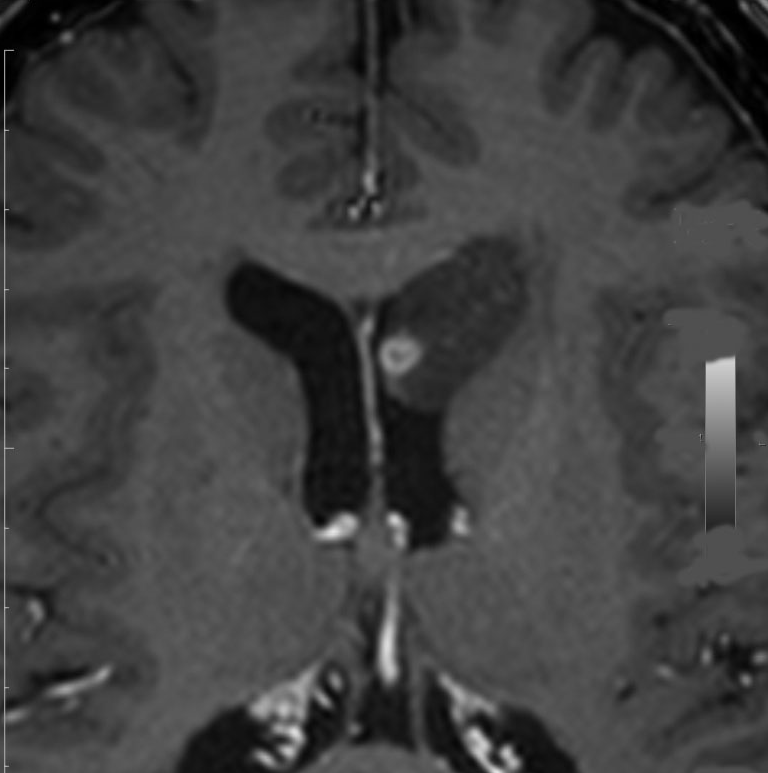

片側性水頭症

左尾状核から発生したものです。モンロー孔を閉塞して,片側性水頭症となっています。腫瘍がトリュフみたいにゴツゴツしているのも特徴です。

下のガドリニウム増強T1では,部分的に増強されます。

もちろん無症状ですが,年齢が若かったので全摘出しました。